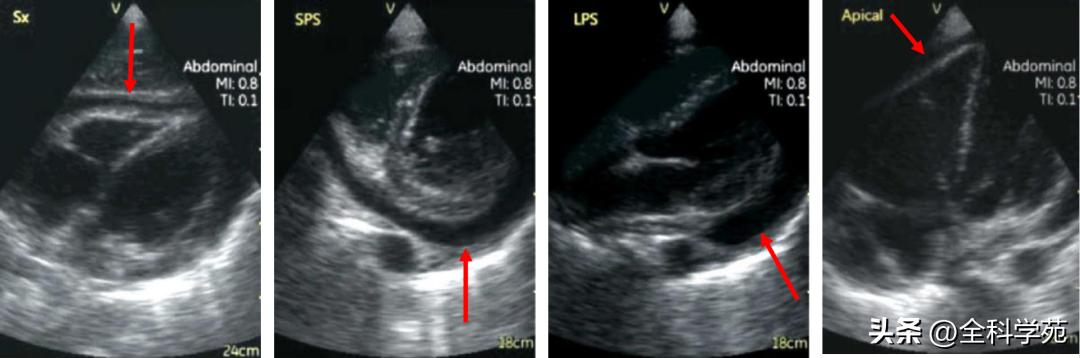

C:心脏彩超: 左心房、右心房增大, 左室射血分数(LVEF)40% ,左室壁厚度14mm,心肌回声不均匀,可见 细颗粒状回声 , 左右心室壁运动均减弱

D:心脏彩超:室间隔及左、右室壁厚度正常, 左室心尖部显示欠佳,可见不规则回声浸润心肌,分界不清 ,局部室壁运动大致正常

3°:心脏彩超: 左室舒张末内径70mm,收缩末内径50mm,射血分数33%。左心及左房增大,左心功能明显减低, 室壁运动欠协调,运动幅度及收缩增厚率弥漫性减低 。

4)心脏彩超:心包腔内微量积液,心包脏、壁层增厚,以右室后壁、侧壁、左室侧壁及心尖部为主, 增厚心包回声增强

4)心脏彩超:剑突下、胸骨旁短轴、胸骨旁长轴及四腔心切面均提示 心包积液 。